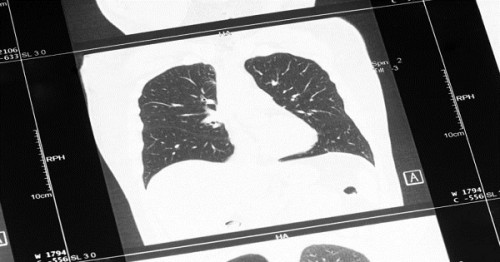

Nguyên nhân đứng thứ 3 gây tử vong trên toàn thế giới là COPD, còn gọi là bệnh phổi tắc nghẽn mãn tính. Đây là một khái niệm dùng để chỉ các bệnh tiến triển ở phổi, ví dụ như khí phế thũng, viêm phế quản mạn tính và hen suyễn dai dẳng. Triệu chứng phổ biến của bệnh COPD là khó thở, khò khè và ho nhiều.

Ung thư khí quản, phế quản và ung thư phổi gây ra khoảng 1.7 triệu ca tử vong vào năm 2016. Ung thư phổi đặc biệt là bệnh ung thư gây tử vong hàng đầu ở Mỹ, ở cả nam gới và nữ giới. Mặc dù ung thư phổi có liên quan đến tình trạng hút thuốc lá, nhưng kể cả những người không hút thuốc cũng có nguy cơ bị ung thư phổi. Đa số các bệnh ung thư đường hô hấp sẽ có cùng các triệu chứng, ví dụ như khò khè và khó thở.